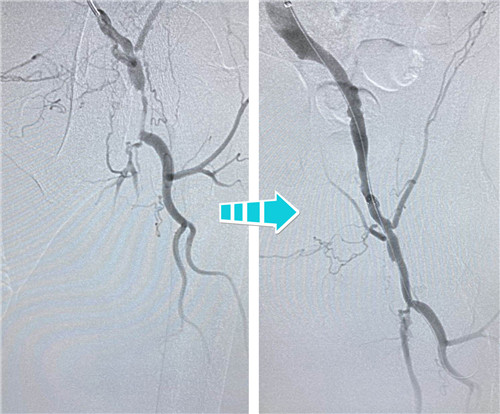

84歲的患者吳老原本只是走路時(shí)感覺(jué)小腿痛,慢慢地,他發(fā)現(xiàn)睡覺(jué)躺下時(shí)也疼得厲害,且有愈演愈烈的趨勢(shì)。入院完善相關(guān)檢查,這才找到腿疼的根源——竟然是血管堵住了!雙下肢血管造影顯示,吳老先生的情況不容樂(lè)觀,右側(cè)髂血管完全閉塞,左側(cè)髂血管重度狹窄,左側(cè)股淺開(kāi)口以下同樣閉塞。如不及時(shí)治療,病情繼續(xù)惡化,皮膚會(huì)慢慢潰爛、發(fā)黑直至壞疽截肢。

身經(jīng)百戰(zhàn)的放射科介入團(tuán)隊(duì),在南京鼓樓醫(yī)院血管外科王煒教授的指導(dǎo)下,決定為吳老先生行兩側(cè)髂血管成形術(shù)。手術(shù)當(dāng)天,選擇經(jīng)左側(cè)肱動(dòng)脈入路,置入90CM長(zhǎng)鞘,在導(dǎo)絲指引下,小心翼翼地通過(guò)左側(cè)股總動(dòng)脈狹窄段,給予球囊擴(kuò)張,精確定位并植入支架,左側(cè)髂血管就此打通??紤]后期患者情況改善,可能還需要處理股淺動(dòng)脈,專(zhuān)家們還預(yù)保留了股淺和股深開(kāi)口。